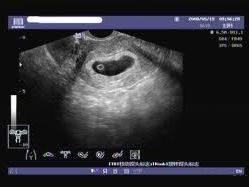

空孕囊是指孕婦在妊娠早期,胚胎發(fā)育異?;蛲V拱l(fā)育,導(dǎo)致孕囊內(nèi)沒(méi)有胚芽或胎心的情況,對(duì)于期待寶寶的家庭來(lái)說(shuō),空孕囊的出現(xiàn)無(wú)疑是一種打擊,了解空孕囊的征兆,早期識(shí)別并采取措施,對(duì)保障母嬰健康具有重要意義,本文將為您詳細(xì)解析空孕囊的十個(gè)征兆,以便您及時(shí)察覺并處理。

通過(guò)B超檢查發(fā)現(xiàn)胚胎未按照正常時(shí)間發(fā)育,如未按時(shí)出現(xiàn)胚芽、胎心等,可能是空孕囊的表現(xiàn)。

羊水是胎兒生長(zhǎng)的重要環(huán)境,如B超檢查發(fā)現(xiàn)羊水過(guò)少或無(wú)羊水,可能是空孕囊的征兆。